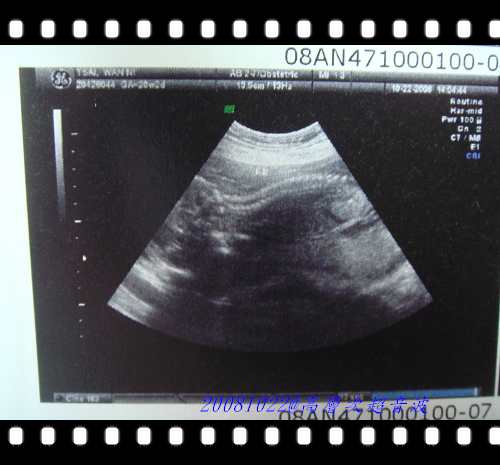

這張照片就是在算寶寶的指頭數目對不對,兩手都有五根指頭....